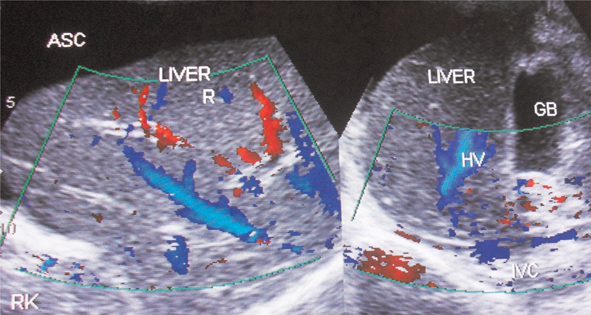

Figure 5. Ultrasonography and color Doppler of a patient with HVCS showing ascites with evidence of chronic peritonitis—Multiple intraperitoneal adhesions. Note the thrombosed, medium-sized branches of portal veins. ASC, ascites. (Copyright: Santosh Man Shrestha).

Fig 6

Figure 6. Ultrasonography and color Doppler of a patient with ascites due to HVCS. IVC shows stenosis at cavo-atrial junction with distal segment dilated. IVC is filled with organized thrombus. There is obstruction to blood flow at the hepatic vein outlets. Note thrombosis of medium-sized tributaries of right hepatic vein. GB, gall bladder; HV, hepatic vein; RHV, right hepatic vein. (Copyright: Santosh Man Shrestha).

Acute onset of high-protein-content ascites in young female patients, especially Caucasians with risk factor for thrombosis, is likely to be due to BCS. BCS patients with myeloproliferative disorders have, on average, higher platelet counts and a larger spleen. US/CD imaging of liver will show features of HV obstruction similar to HVCS, but IVC will be normal or narrowed by caudate lobe enlargement without organized thrombus along its posterior wall, bacterial peritonitis or edematous gallbladder wall.